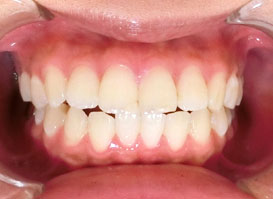

口元症例③

- 性別:男性

- 年齢: 33歳

- 治療期間:1年10ヵ月

- 治療内容:第1小臼歯(4番目の歯)を4本抜歯し、マルチブラケット装置で矯正することで上の出っ歯、下の前歯のデコボコが改善されました。

最も気にされていたお口元の突出感もなくなり、美しい『E-line』なりました。 - 費用:892,500円(税込)

- リスク・副作用:治療後の後戻り・歯根吸収・歯髄壊死・歯肉退縮が生じる場合がございます。